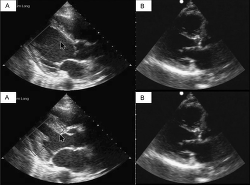

From the parasternal long axis (PSLA), the clinician can observe the right ventricular outflow track, the left ventricle, the ventricular septum, the posterior wall of the left ventricle, and the anterior and posterior mitral leaflets (Perera et al., 2010). Although from the PSLA, the ED clinician will be able to appreciate an enlarged right ventricle, the four-chamber view is the recommended window to assess difference in dimension between the right and left ventricles. In a normal clinical setting, the right ventricle is half or two third the size of the left ventricle (Perera et al., 2010; Perera, Lobo, Williams, & Gharahbaghian, 2014). Acute and chronic conditions that may cause alterations to this ratio are discussed later.

The next component of examining the pump includes assessing the contractility of the heart. This requires evaluation of the mitral valve and global left ventricular function (Wacker & Winters, 2014). The clinician should closely examine the motion of the anterior leaflet of the mitral valve to determine whether it is making contact or coming close to making contact with the interventricular septum of the heart (Perera et al., 2010; see Figure 10A). In a normal state of contractility, the anterior leaflet of the mitral valve is seen snapping or flipped open against the interventricular septum (Perera et al., 2014). In a patient with poor activity, the leaflet does not come into contact with the interventricular septum during systole (Perera et al., 2010; see Figure 10B).

Figure 10 - Click to enlarge in new windowFigure 10. (A) Normal movement of the anterior leaflet of mitral valve. (B) Abnormal movement of the anterior leaflet of mitral valve. Photograph reproduced with permission from SonoSim, Inc.

The contractility of the heart is then assessed by observing the contraction and relaxation of the left ventricle. To do so, the clinician focuses on the tight opposition of the posterior wall of the left ventricle and the interventricular septum (Mcdonald, Feigenbaum, & Chang, 1972; Perera et al., 2010). As the ventricle is going through systole, the clinician observes for approximation of the posterior wall of the left ventricle to the interventricular septum. A normal finding as the cardiac cycle goes through end diastole is for the posterior wall of the left ventricle and interventricular septum to separate from one other, allowing for blood filling (Mcdonald et al., 1972; Perera et al., 2010; see Figure 11A). However, in a patient with poor contractility, these two walls may not approximate one other or demonstrate this tight opposition (Perera et al., 2010; see Figure 11B). During this portion of the examination, heart contractility is categorized into one of four grades: normal; mild to moderately decreased; severely decreased; or hyperdynamic, which is more contractile than normal. The hyperdynamic state is an abnormal condition usually seen during compensation of distributive shock or hypovolemia (Perera et al., 2014).

Figure 11 - Click to enlarge in new windowFigure 11. (A) Normal left ventricular wall motion. (B) Abnormal ventricular wall motion. Photograph reproduced with permission from SonoSim, Inc.

A clinician should be especially alert for a pericardial effusion that leads to compression of the right ventricle. This finding is pathognomonic of a tamponade (Gonzalez et al., 2019; Perera et al., 2010; Wacker & Winters, 2014). In this setting, the right ventricle has what is known as a paradoxical movement. The right ventricle appears contracted or collapsed rather than dilated during the diastolic phase of the cardiac cycle (Perera et al., 2014; (see Figure 12). Inversely, the right atrium of the patient with a tamponade will be collapsed during systole (Smith, Watnick, & Ferre, 2017). In addition, patients experiencing a pericardial tamponade commonly develop plethoric inferior vena cava, or little variation with the respiratory cycle. This finding is considered very sensitive (95%-97%) for the diagnosis of a tamponade (Alerhand & Carter, 2019).

When evaluating for obstructive conditions, the clinician must also assess for right ventricular strain. This problem is diagnosed by evaluating the overall size of the right ventricle (Wacker & Winters, 2014). As stated previously, the normal finding is for the right ventricle to be smaller than the left ventricle. In cases of pulmonary hypertension or a very large PE, the pulmonary arterial pressure increases, dilating the right ventricle. As a result, the right ventricle will appear larger than the left ventricle on the ultrasound scan (Perera et al., 2010, 2014; (see Figure 13). This right-sided ventricular overload caused by increased pulmonary pressures consequently decreases amount of blood arriving from the pulmonary vasculature to the left ventricle. In severe cases, the left ventricle may appear collapsed, demonstrating the decreased filling of this chamber. However, the clinician needs to be aware that some conditions can lead to chronic enlargement of the right ventricle and can be confused for ventricular straining. Conditions such as chronic obstructive pulmonary disease and chronic pulmonary hypertension can lead to these changes. Of note, in these cases, the clinician normally observes enlargement of the ventricle itself with dilation rather than dilation alone, which is more commonly seen in acute straining patterns, such as PE. The clinician should consider ventricular wall size as a point of differentiation: In acute conditions leading to straining, the wall will be less than 5 mm. In the case of chronic conditions, this measurement tends to be greater than 5 mm (Perera et al., 2010, 2014).

Figure 13 - Click to enlarge in new windowFigure 13. Right ventricle straining pattern. LV = RV = right ventricle. Photograph reproduced with permission from SonoSim, Inc.